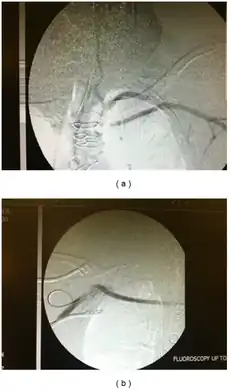

Restoration of flow in the left subclavian artery across a propaten graft from the right subclavian artery.